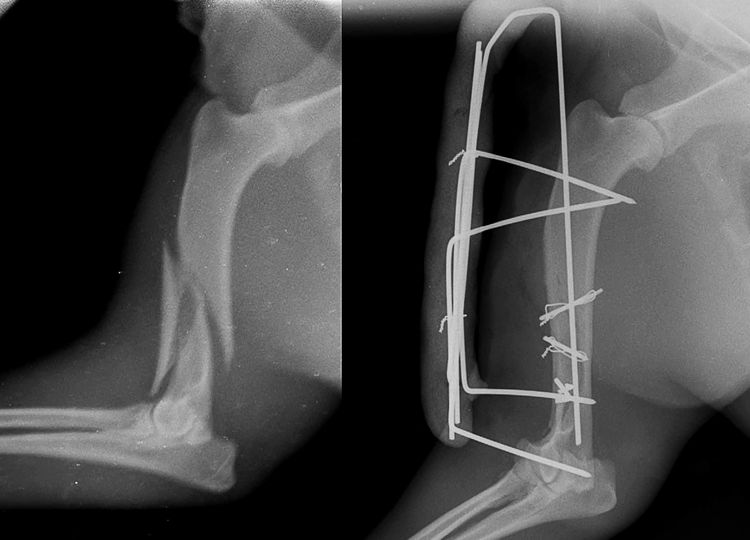

La plupart des fractures des membres chez le chien (environ 90 %) nécessitent une intervention chirurgicale. L'ostéosynthèse (fusion osseuse) est réalisée à l'aide de broches, d'agrafes, de vis et de plaques. Ces dernières années, grâce aux progrès technologiques, les vétérinaires utilisent désormais des dispositifs en polymère, en plus des dispositifs métalliques.

- L'appareil de Kishner. Une structure composée d'une tige métallique et de tiges autotaraudeuses est utilisée pour les fractures intra-articulaires.

- L'appareil d'Ilizarov se compose de broches et d'anneaux métalliques qui maintiennent fermement en place les fragments d'os.

- Fixation interne. Intervention la plus complexe. Le chirurgien doit posséder les qualifications et l'expérience nécessaires pour la réaliser efficacement. Des broches sont insérées directement dans les os longs. Elles ne sont pas retirées et restent en place à vie.